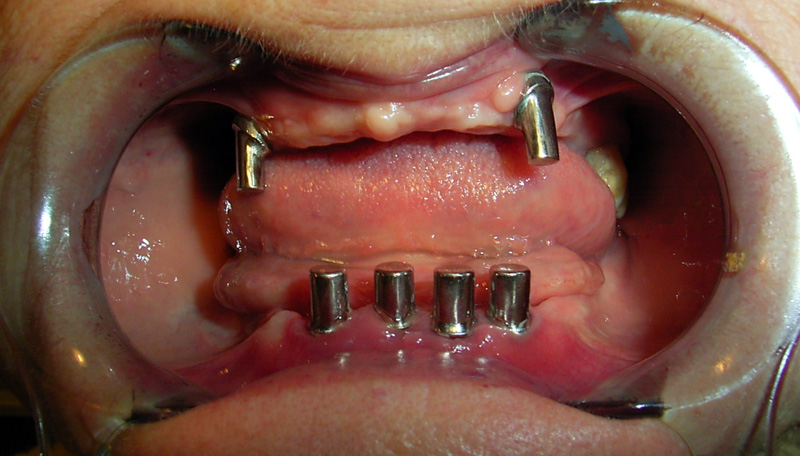

Implante - Galerie Foto

Caz I